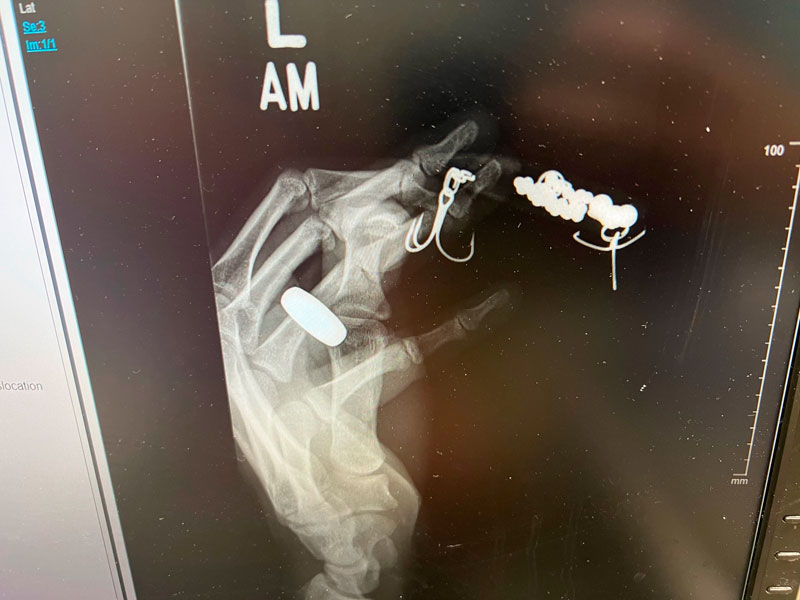

You never know what you might catch when you drop a hook in Louisiana waters. But when Victor Moran caught this peacock bass from Bayou St. John, it was certainly a surprise. Unfortunately, he didn’t get to keep the fish for further indentification because he got the hook in his finger and had to make a trip to the emergency room. He did report it to the LDWF for further investigation. They plan to electrofish the area to see if there are more.